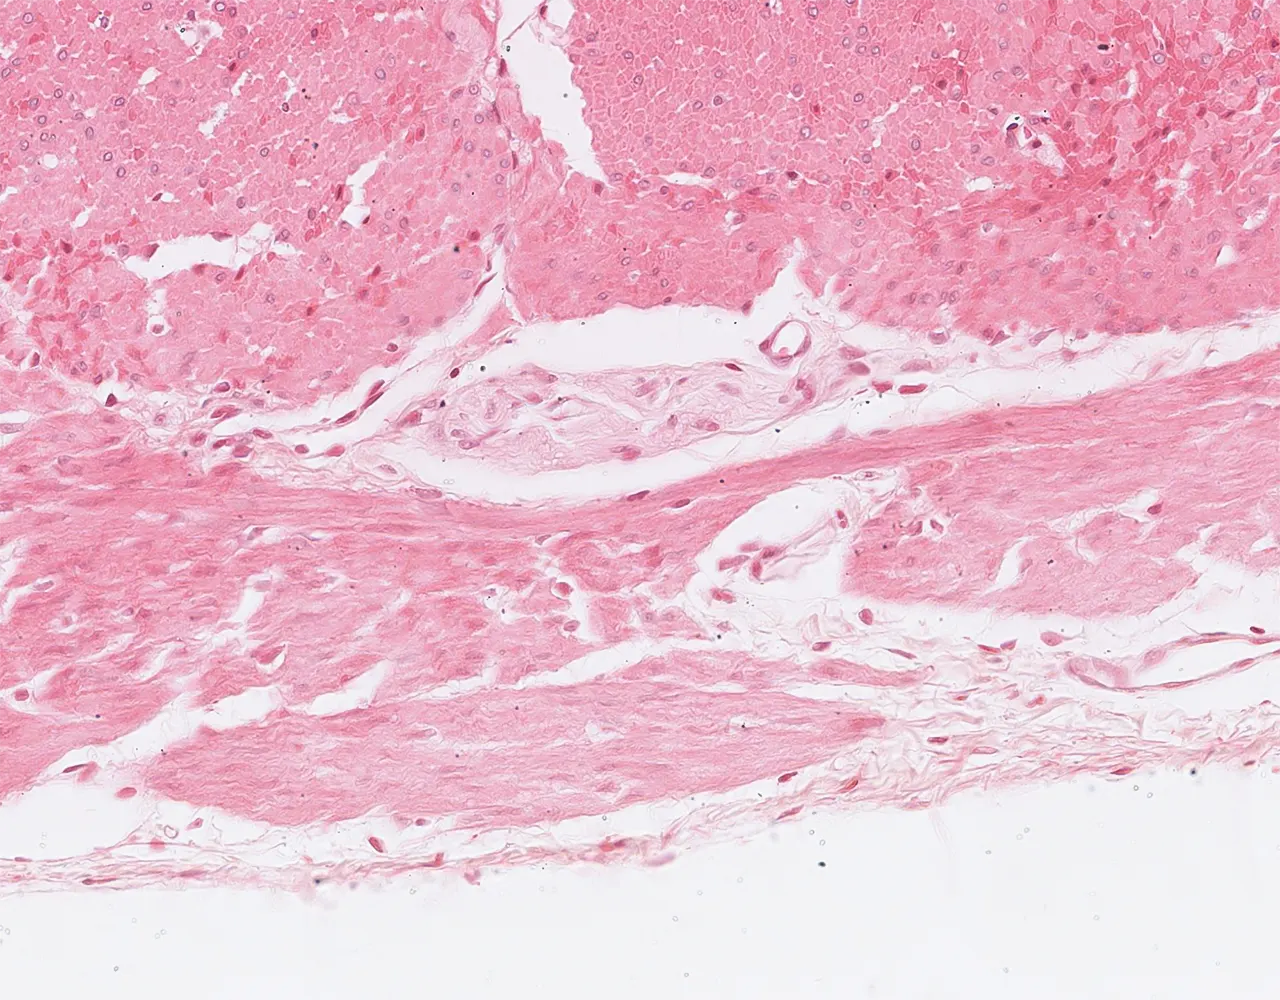

- The wall of the stomach is composed of four layers, from the innermost to the outermost: mucosa, submucosa, muscularis propria, and serosa.